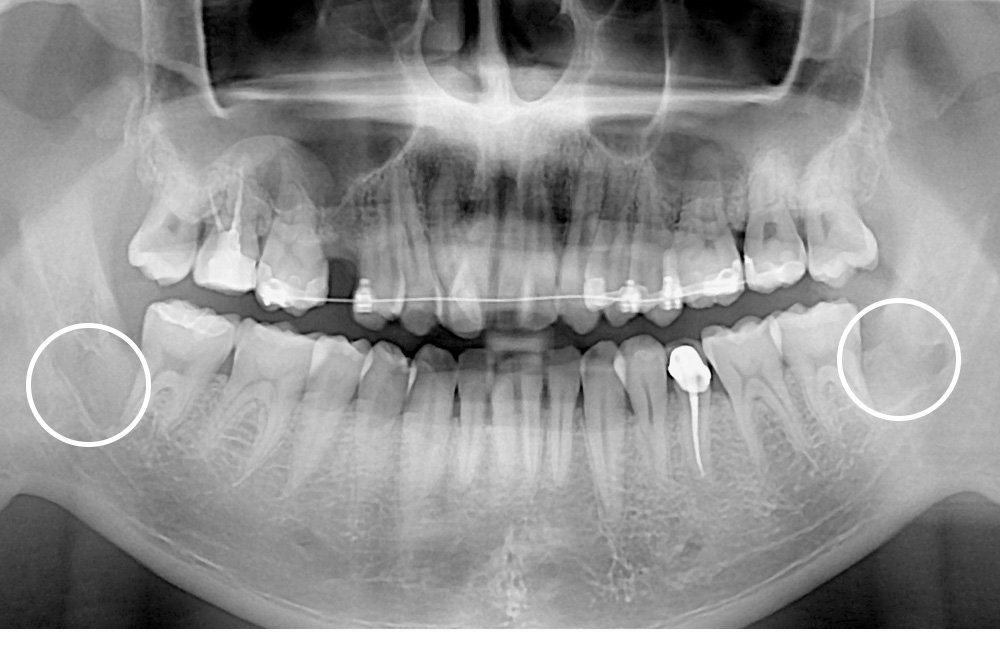

[사랑니] 매복 사랑니 발치

치료전 : 2017-10-18

치료후 : 2017-11-02

세종치과는 구강악안면외과학 박사이신 원장님이 발치하는 치과입니다.